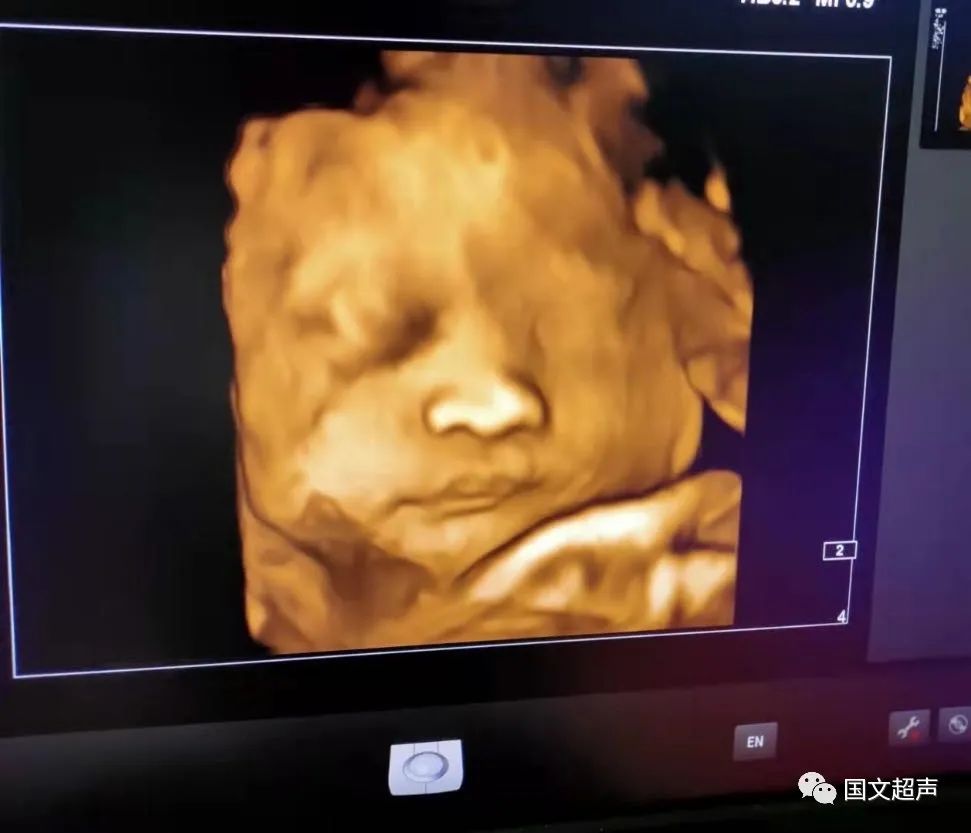

一.飛利浦EPIQ7高端四維彩超

我院目前使用的是飛利浦EPIQ7高端四維彩超,它擁有高品質(zhì)自動成像分析技術(shù),分辨率及清晰度高,可以較清晰的顯示宮內(nèi)胎兒的生長發(fā)育情況,為診斷胎兒先天性畸形,如唇裂、脊柱裂、顱腦發(fā)育異常、骨骼發(fā)育異常、心血管畸形等提供準(zhǔn)確的科學(xué)依據(jù)。